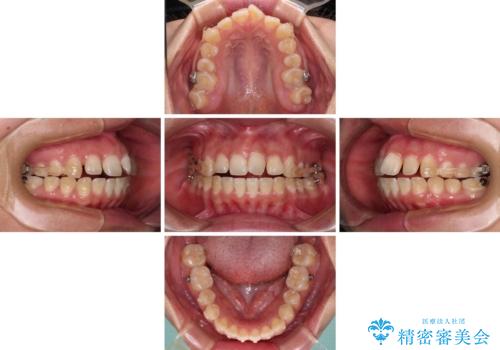

口元の閉じにくさを改善するためには、上顎臼歯を後方に移動させた咬み合わせにする必要があります。

奥歯の咬み合わせを改善しながら、並行してインビザラインで歯列を整えることとしました。

カリエールディスタライザーを併用したことで、確実かつ短期間で治療を終えることができました。